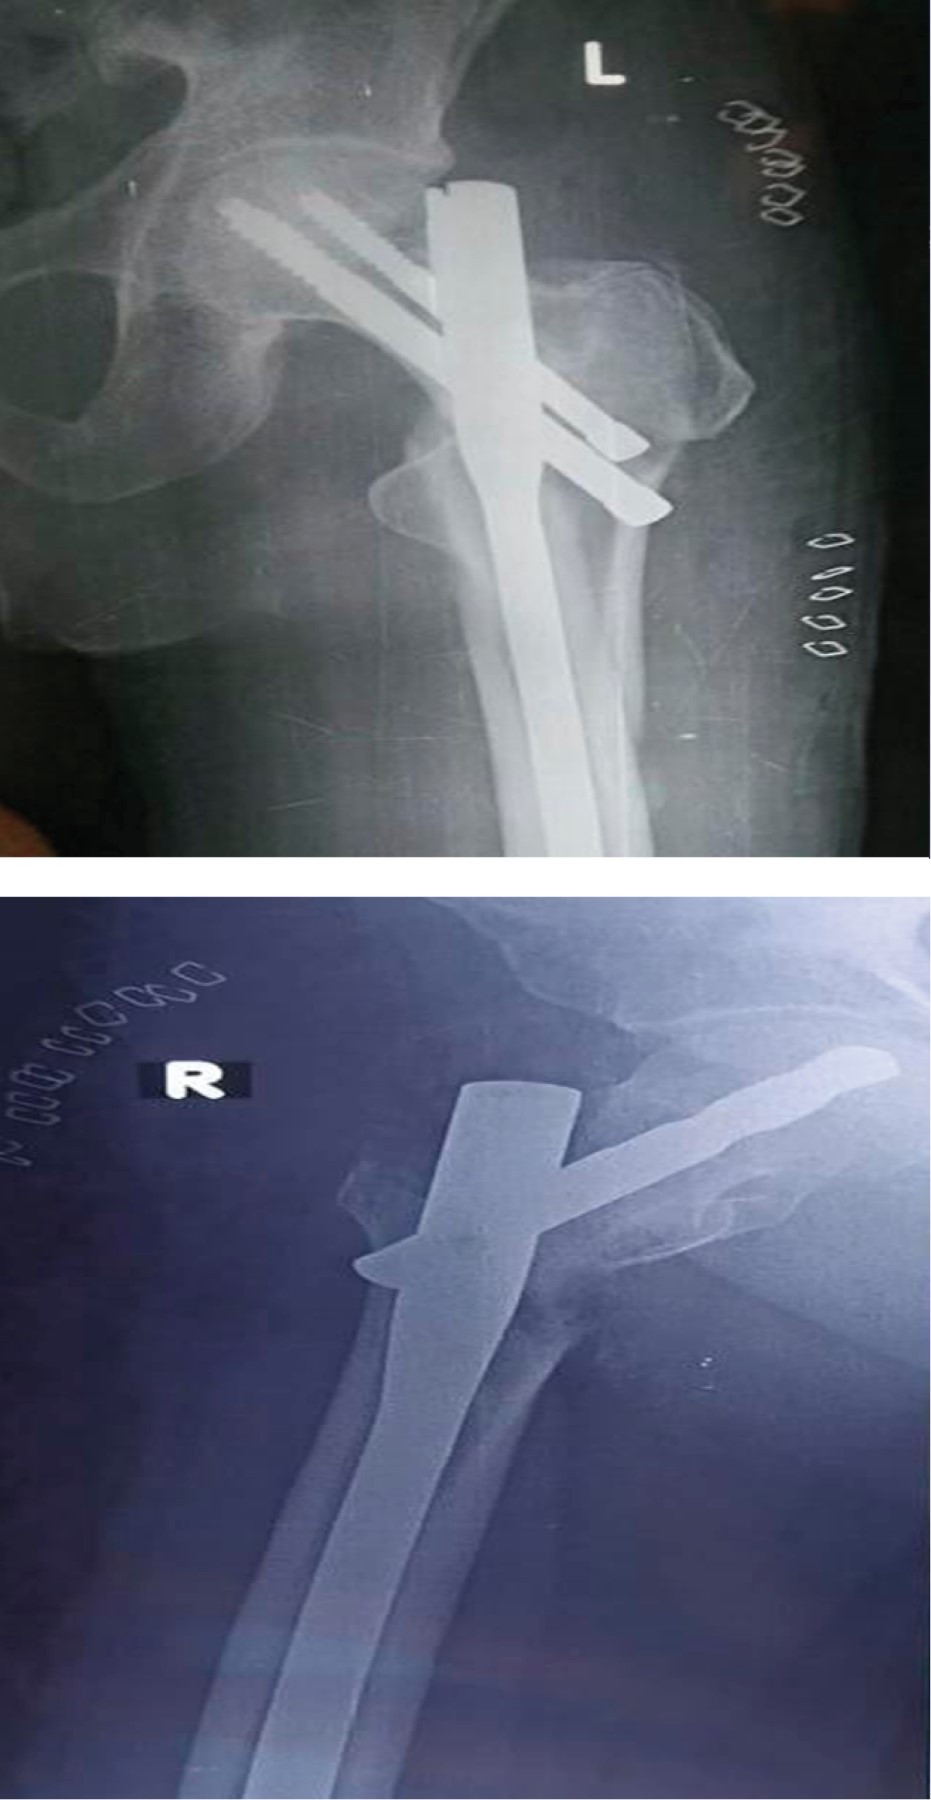

Implant related complications like screw back out (Figure 1), guide wire breakage (Figures 2 and 3), Z effect (Figure 4), TAD outliers (Figure 5) were more in PFN group whereas lateral screw protrusion, locking mechanism failure and barrel disengagement was more in PFNA2 group as shown in Figures 6, 7, 8 and 9. Neck shaft valgus outliers are more common in PFN group (Figure 10).

Implant-related complications, such as screw back-out, guidewire breakage, and proximal protrusion, were more pronounced in the PFN group, whereas lateral screw protrusion and medial migration were notable in the PFNA2 group.24 Lateral screw protrusion was observed in four patients in the PFNA2 group and one patient in the PFN group at the final follow-up in our study. Hu et al suggested a morphological mismatch in the Asian population between the proximal fragment of PFNA2 and the greater trochanter, leading to post-operative lateral trochanter pain.24

Maintaining the neck-shaft angle difference between the operated and normal side to less than 5° is necessary for better outcomes.29 In our study, varus malalignment and Limb Length Discrepancy (LLD) were associated with a neck shaft angle difference of 10° and 5° in the PFNA and PFN groups, respectively. Neck shaft angle outliers were more common in the PFN group (Figure 10), likely to achieve better proximal screw purchase and to avoid postoperative varus collapse, whereas outliers in TAD were more common in the PFNA group, possibly due to difficulty in differentiating between the screwdriver tip and screw head while engaged.